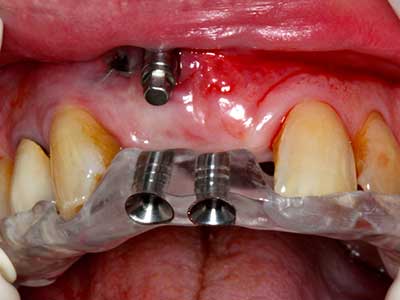

Piezo surgery has additional advantages when harvesting bone blocks. In addition to the high precision with osteotomy described above, the use of the thin saw tips specifically minimizes loss of material. Greater loss of material during harvesting can be expected with the thicker instrument tips, particularly when using Lindemann drills (Lakshmiganthan, Gokulanathan et al. 2012). The basal separation, which is necessary particularly for retromolar block transplants, is simplified by specially designed rectangular saws, with the result that piezo surgery is viewed as a precise, simple and safe procedure for harvesting retromolar bone blocks (Happe 2007) (Fig. 1-12).